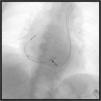

A veia cava superior esquerda persistente (VCSEP) é a malformação venosa congénita torácica mais frequente e o seu diagnóstico costuma ser incidental. Casos clínicos demonstrativos de implantação de pacemakers de dupla câmara (DDD), cardioversores desfibrilhadores implantáveis e sistemas de ressincronização cardíaca através desse acesso venoso foram já descritos na literatura. Contudo, na grande maioria dos casos apresentados o posicionamento do eletrocater (ECT) ventricular direito (ECT‐VD) ficou restrito ao apéx do ventrículo direito (VD). Até ao momento estão descritos na literatura apenas quatro casos de posicionamento do ECT VD no trato de saída do VD através da VCSEP. Os autores apresentam o caso de uma doente do sexo feminino, de 79 anos, com diagnóstico de síncope e bloqueio de ramo esquerdo proposta para implantação de pacemaker DDD. Durante o procedimento obteve‐se acesso venoso pela veia cefálica esquerda, verificou‐se que o ECT progredia à esquerda da coluna vertebral, sugestivo da presença de VCSEP. Através desse acesso foi possível implantar sequencialmente o ECT‐VD no trato de saída do VD e o ECT auricular no apêndice auricular direito, ambos com sistema de fixação ativa (Figura 1).